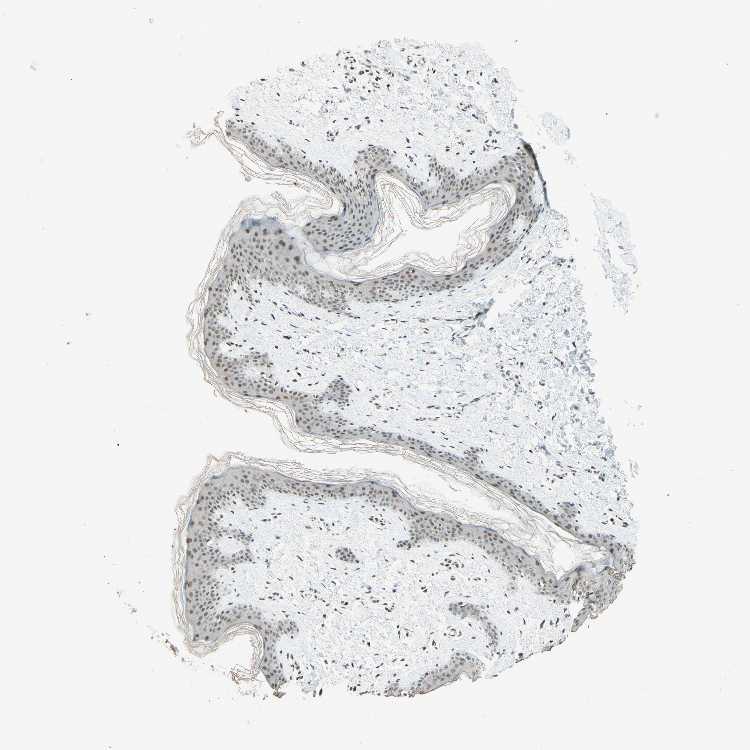

SKIN 1 - Antibody stainingi

Antibody staining in the annotated cell types in the current human tissue is reported as not detected, low, medium, or high, based on conventional immunohistochemistry profiling in selected tissues. This score is based on the combination of the staining intensity and fraction of stained cells.

Each image is clickable and will lead to virtual microscopy that enables deeper exploration of all samples and also displays staining intensity scores, fraction scores and subcellular localization as well as patient and tissue information for each sample.

Antibody HPA018248Antibody HPA019127Antibody CAB009196

Langerhans -LowLow

Cells in basal layer Low--

Cells in corneal layer Not detected--

Cells in granular layer Low--

Cells in spinous layer Not detected--

Eccrine glands Not detected--

Endothelial cells Not detected--

Extracellular matrix Not detected--

Fibroblasts -LowLow

Fibrohistiocytic cells Low--

Hair follicles Not detected--

Keratinocytes -MediumMedium

Langerhans cells Not detected--

Lymphocytes High--

Melanocytes MediumLowNot detected

Vascular mural cells Not detected--